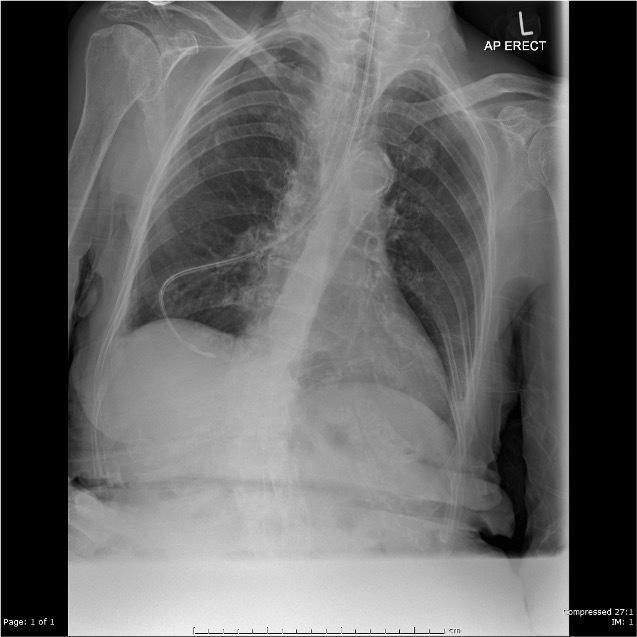

Pneumothorax

**tension pneumothorax** Small chest drain in situ Basal atelectasis left Surgical emphysema within mediastinum and soft tissue